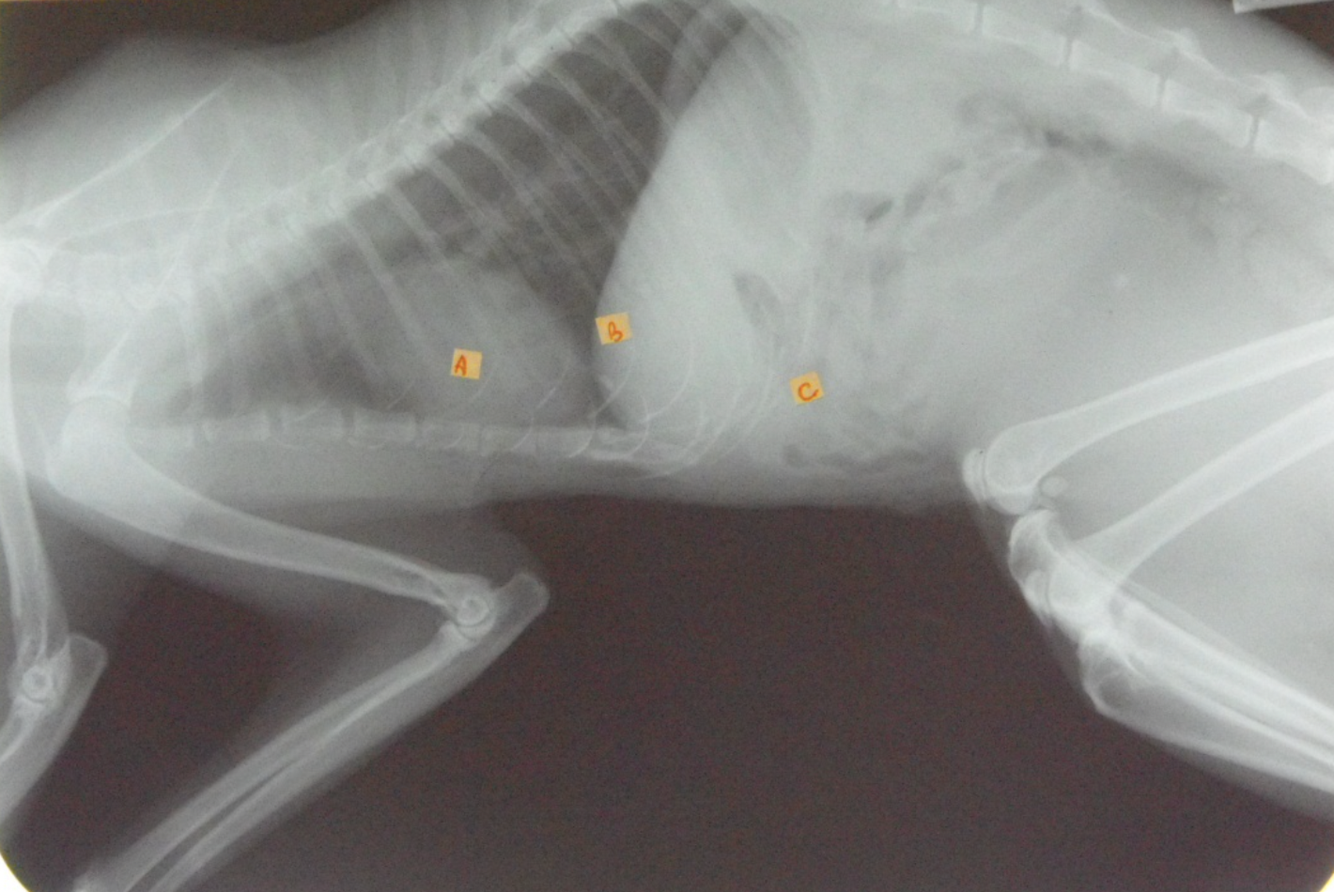

identify the structures of the cat thorax

A= heart

B= diaphragm

C= liver

how does the shape of the cat thorax differ than the dogs

shape: narrow and steep, heart sits more at an angle and it is positioned more caudally (4th-7th intercostal space) also little of the heart is covered by the forelimb as the triceps reaches no further than the 4th rib

Identify Manubrium of sternum, First rib, Apex of heart, Base of heart, Diaphragm and First lumbar vertebra

Again note the shape of thoracic cavity. How does it compare to that of the dog?

Narrower particularly about the thoracic inlet